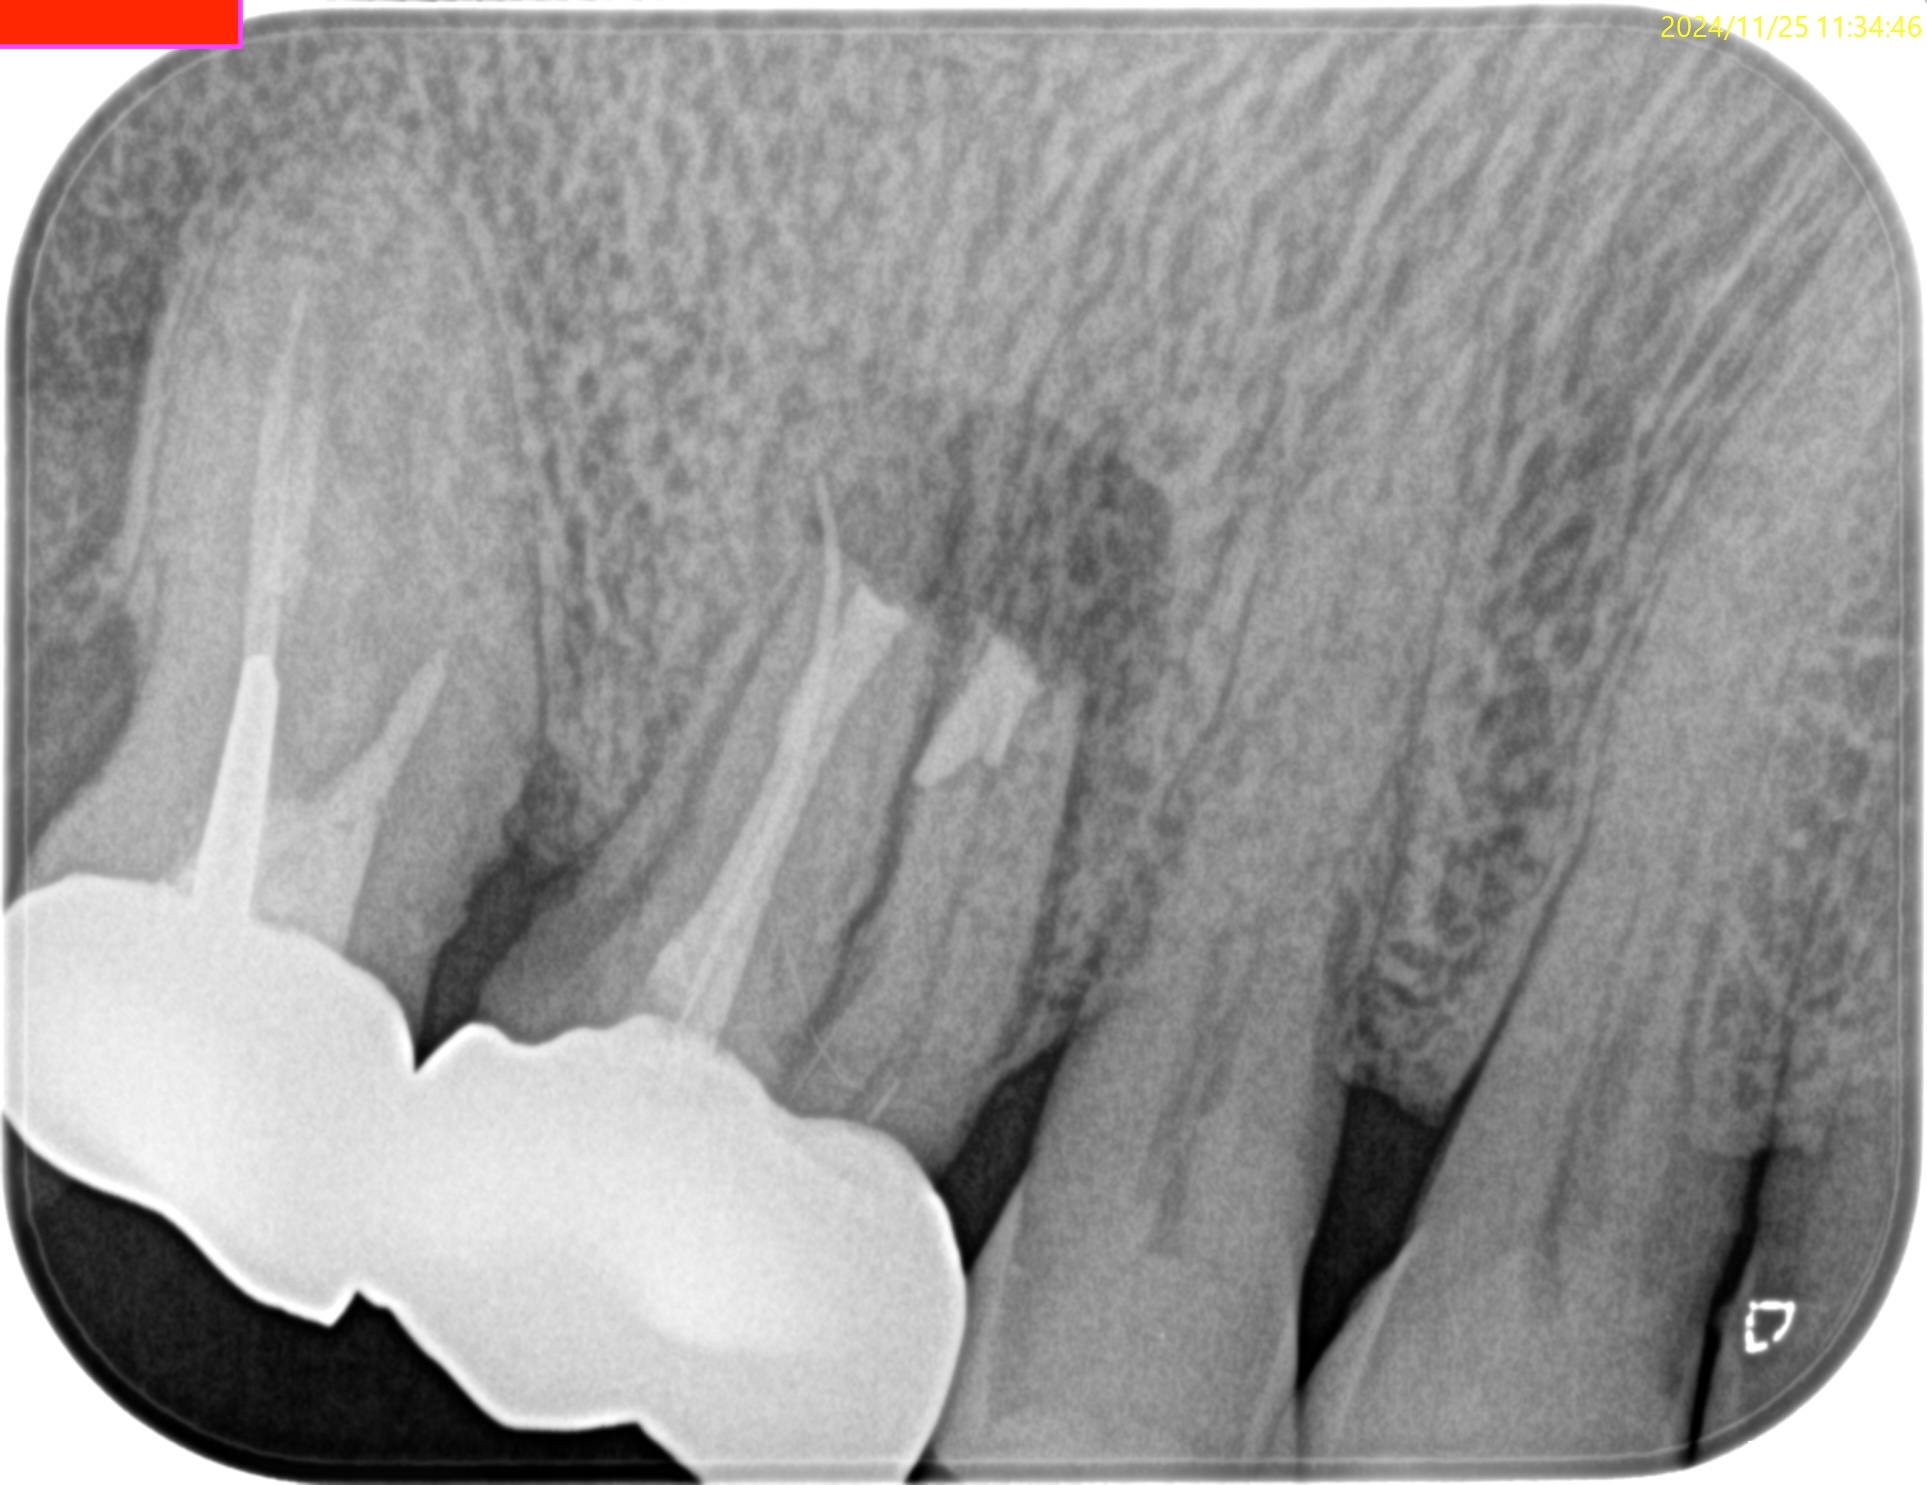

Pre-op PA(2024.11.25)

MBは形成されていない。

ということは通常は根管治療だがSinus tractの存在が治療をApicoectomyへ流れさせている。

MB

DB

B

MBはOff-Axsisで穿孔もしたであろうが問題ないと判断し、縫合して終了した。